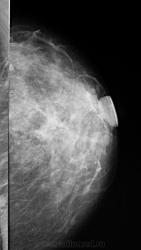

- https://radiomed.ru/sites/default/files/styles/case_slider_image/public/user/1787/P1010699.JPG?itok=-hMVVlD6

На фоне фиброзной мастопатии определяются с обеих сторон рассеянные микрокальцинаты и мелкие стромальные, а справа в в/н квадранте подозрительные сгруппированные - нужна пункция